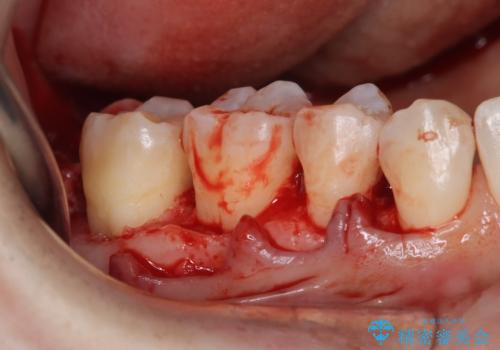

- 定期的にクリーニング(保険適応)に通って頂いている患者さんです。歯周ポケットが4ミリあったため歯茎を開いて歯石を除去するためにオープンフラップ術を行うことにしました。

歯周ポケットがそれほど深くない患者さんでしたが、いざ歯茎を開いてみるとそこにはたくさんの歯石がありました。もし歯周ポケットが4ミリだからと言って放置していれば数年後には、沢山の骨が無くなっていたことが予期出来ます。現段階で歯茎の下にある歯石を除去することにより骨が無くなることを予防する事が出来ました。